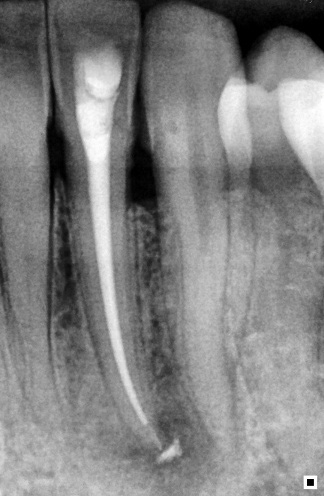

M. M. D., a 34-year-old female patient, visited the dental clinic at Escola Educação Inteligente of Londrina for an evaluation and treatment of tooth 32. During anamnesis and clinical examination, the patient reported that the tooth had an acute abscess approximately a month before (Figure 1).

Figure 1: Initial radiograph